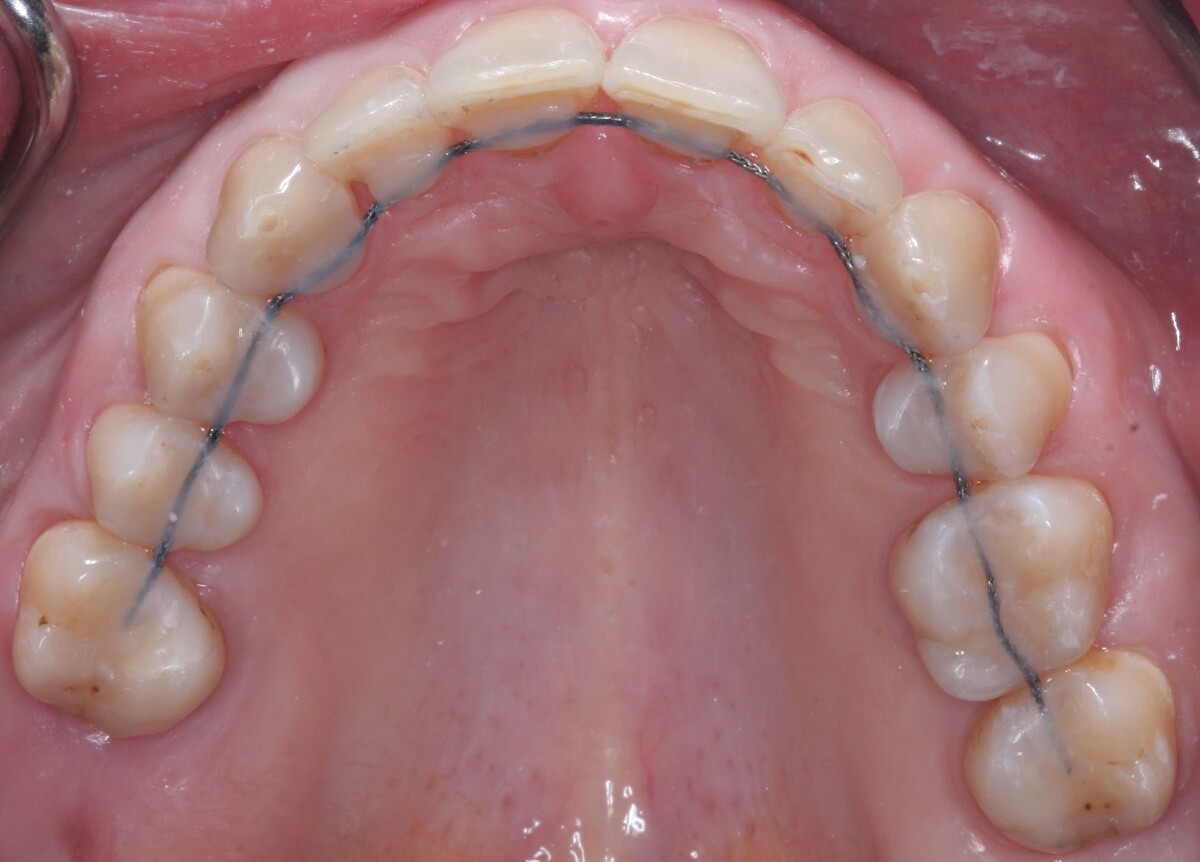

Фото

Ретейнеры — это устройства, которые поддерживают результаты ортодонтического лечения. После снятия брекетов многие пациенты сталкиваются с возвращением зубов в прежнее положение. Ретейнеры помогают сохранить правильное расположение зубов и предотвращают их смещение.

► Несъемные

- Внешне напоминают дугу, тонкую, незаметную, удобную, либо ленту, или волокнистую систему.

- Выполняются из современных металлов.

- Устанавливаются изнутри зубного ряда с применением особого клеящего состава.

- Крепятся к молярам.

- Фиксируются специальным композитным материалом.

- Требуют регулярного наблюдения ортодонта. Врач оценит состояние зубов, особенно моляров, к которым изделия крепятся.